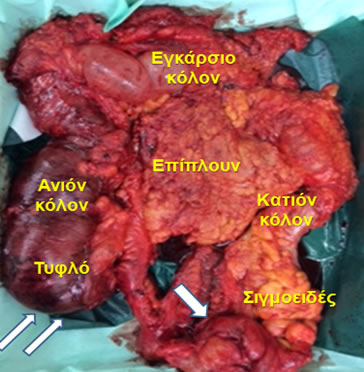

Εικόνα 13.

Παρασκεύασμα εκτεταμένης δεξιάς κολεκτομής που έγινε για καρκίνο της μεσότητας του εγκαρσίου κόλου.

- Ειλεοκολική αρτηρία. 2. Μέση κολική αρτηρία. 3. Ανιόν κλάδος αριστερής κολικής αρτηρίας. 4. Επιχείλιος αρτηρία. 5. Τελικός ειλεός. 6. Δεξιό κόλον. 7. Ηπατική καμπή. 8. Εγκάρσιο κόλον. 9. Σπληνική καμπή

(Από το προσωπικό αρχείο του Γ. Θεοδωρόπουλου)

Εικόνα 14.

Παρασκεύασμα υφολικής κολεκτομής που έγινε για αποφρακτικό καρκίνο σιγμοειδούς (μονό βέλος), που οδήγησε σε ισχαιμία του δεξιού κόλου και διάτρηση του τυφλού (διπλό βέλος) καρκίνο της μεσότητας του εγκαρσίου κόλου.

(Από το προσωπικό αρχείο του Γ. Θεοδωρόπουλου)